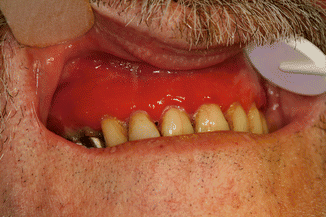

Fig. 35.3

The tweezers sign is demonstrated on the gums